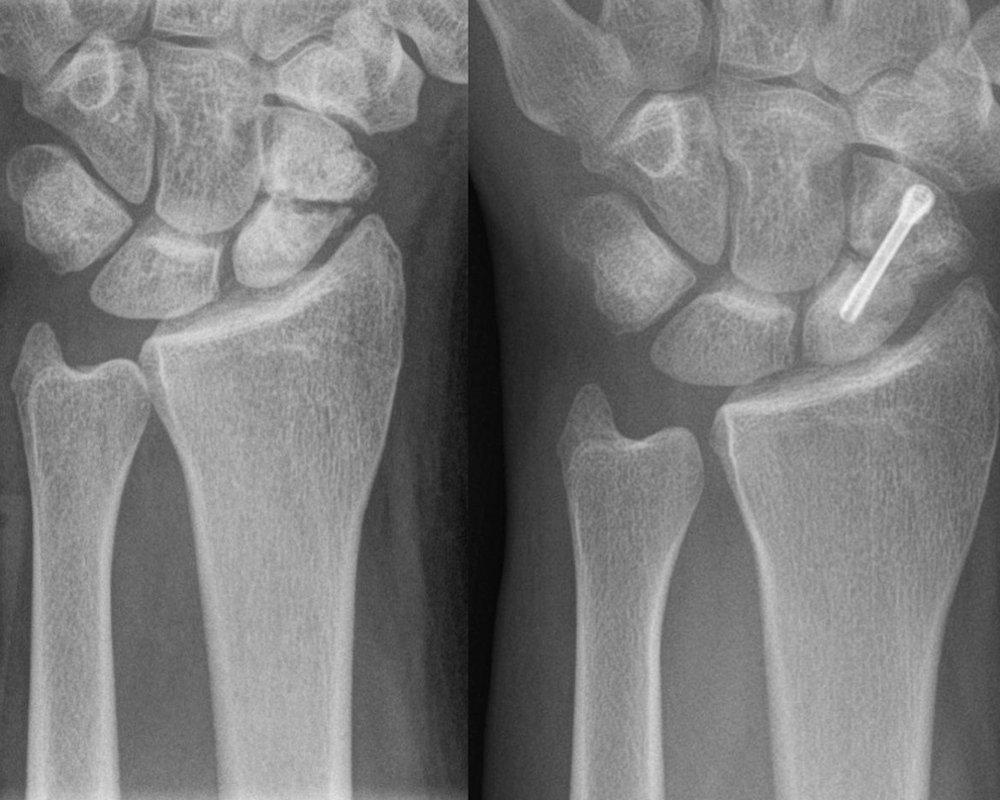

Новое исследование, представленное в журнале The Lancet, показало, что использование гипса так же эффективно при лечении переломов ладьевидной кости запястья, как и хирургическое вмешательство. Ученые подчеркивают, что при таких травмах первоначально нужно рассматривать накладывание гипса, и только при отсутствии заживления рекомендовать пациенту операцию.

В основе исследования лежат данные ортопедических отделений 31 больницы Великобритании за 2013-2016 годы. В общей сложности было зарегистрировано 439 взрослых пациентов с переломом ладьевидной кости запястья.

Пациенты, которые согласились принять участие в исследовании, были случайным образом разделены на две группы: оперативное вмешательство или наложение гипса (если повязка не срабатывала в течение шести недель, пациентам предлагалась операция).

Через год после травмы участники были оценены по ряду факторов, включая боль и функцию запястья, заживление костей, осложнения после лечения и среднее количество потерянных рабочих дней.

При оценке боли пациенты в хирургической группе набрали 12 баллов, а в гипсовой 14 из 100. Однако это различие не является статистически значимым. Количество потерянных из-за травмы дней составило 17 и 18 соответственно. Также не было существенной разницы в количестве переломов, которые не зажили должным образом: 2 процента для группы с операцией и 4 с гипсом. Однако пациенты, перенесшие операцию, чаще сталкивались с осложнениями: 12% против двух.